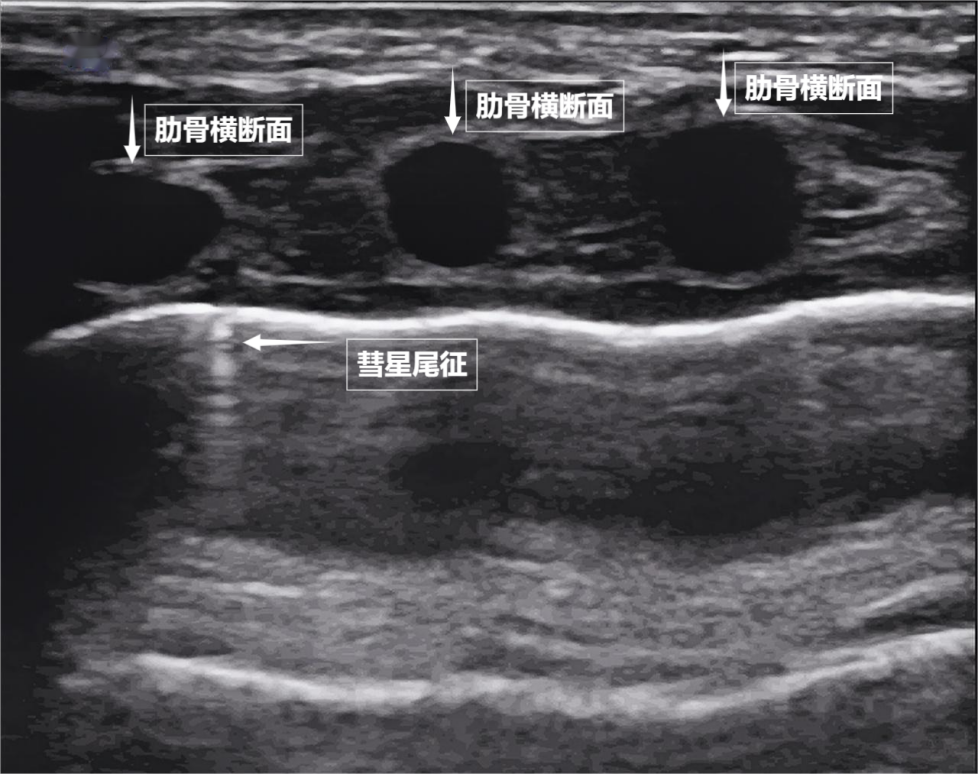

如果我们把超声图像调成实时动态模式,把“照片”变成“电影”,更神奇的一幕出现了。随着呼吸,胸膜线会随胸廓运动轻柔滑动,这就是“肺滑动征”。它意味着肺与胸壁正紧密相依、自由顺畅地呼吸。若肺与胸壁间有气胸或胸腔积液,这种滑动会消失。有时,在胸膜线下方还会出现细小的亮白色闪烁点,称为“彗星尾征”(见下图)。其少量、孤立出现时,通常是正常肺小叶间隔的反射,无需担心。

▲图为正常新生儿肺部超声表现